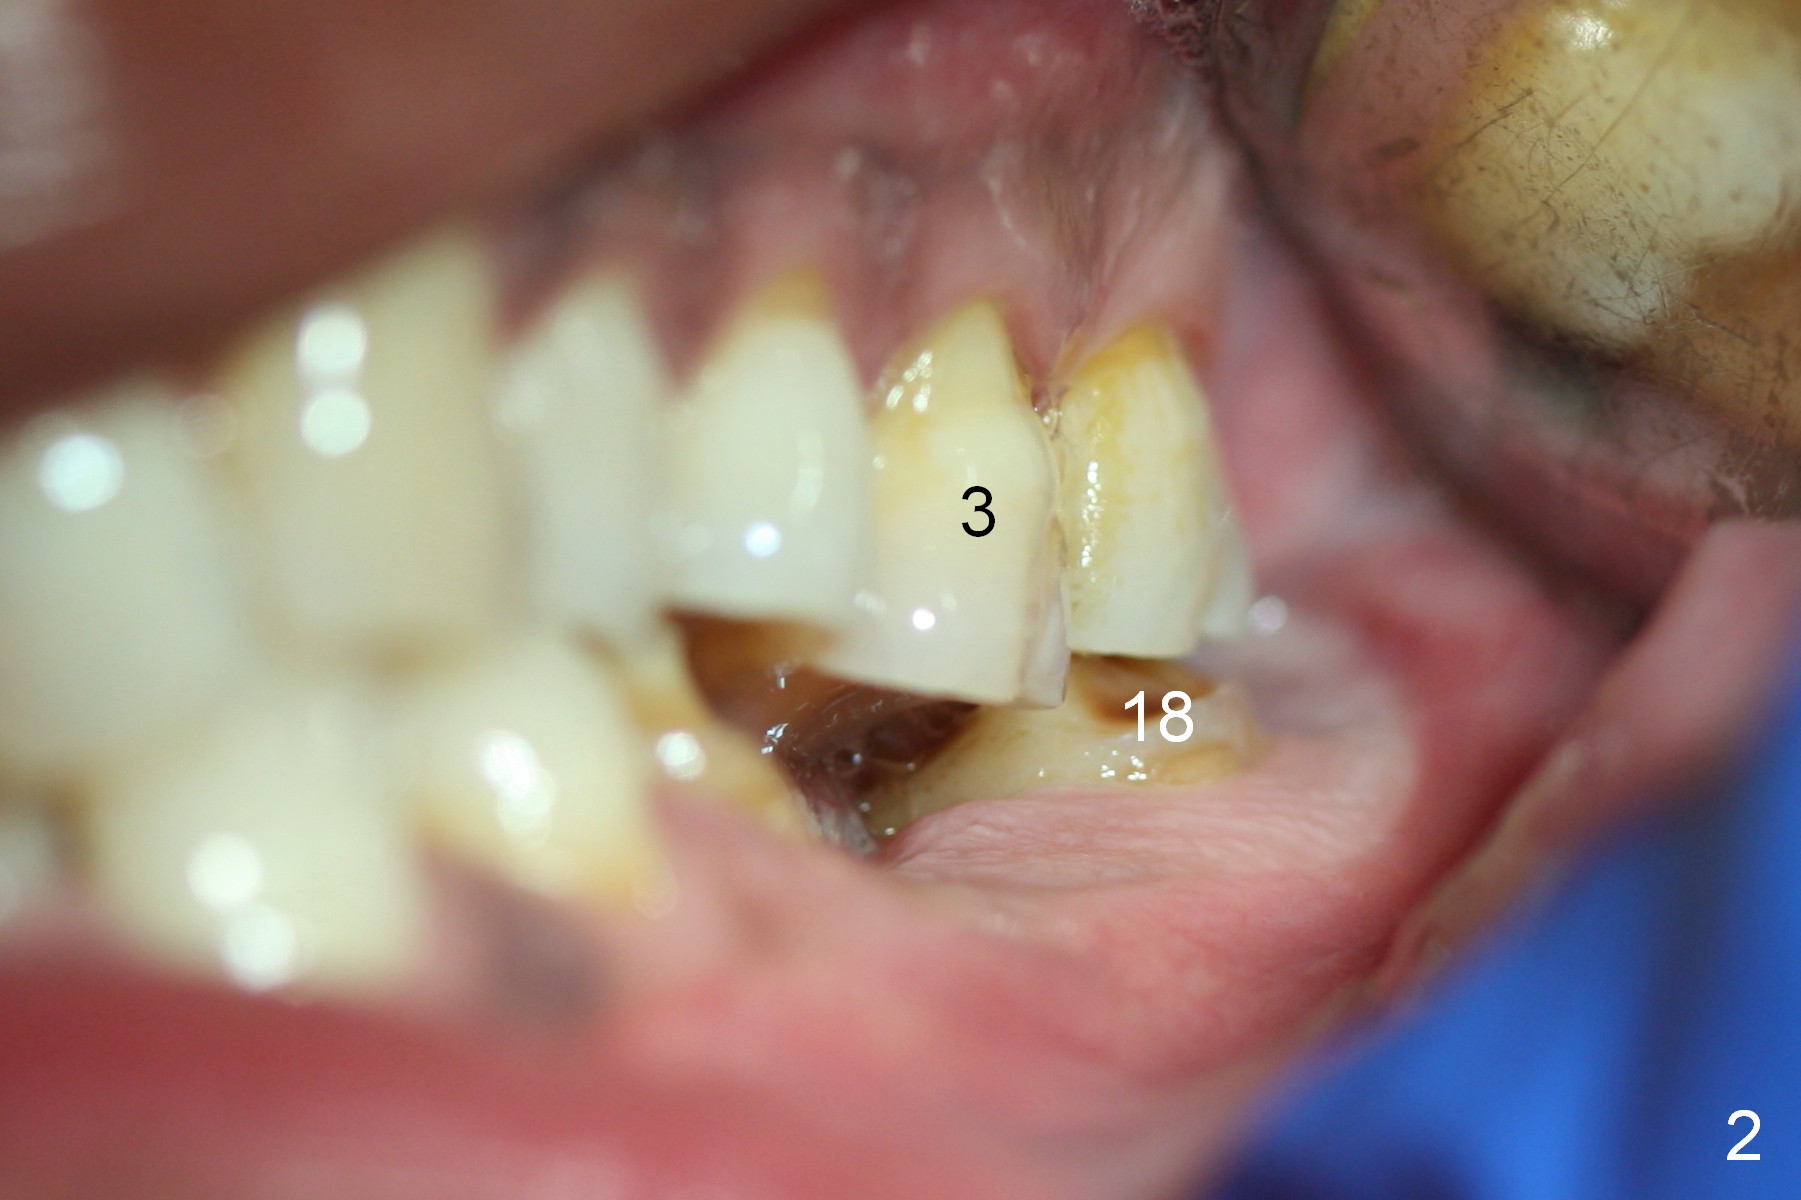

When the patient returns for implant placement, he is pleased to let us know that he has stopped smoking for a week. The edentulous ridge at #19 looks wide (Fig.1). The tooth #3 is supraerupted, while there is no clearance between the abutments (#18 and 20) and the opposing dentition (Fig.2). After incision, the ridge is confirmed to be wide with the aid of implant positioners. The bone is felt soft during initial osteotomy (Fig.3). Attention is being paid to correcting the trajectory. Under prep is ignored. When a 5.9x10 mm implant is placed, the insertion torque is between 25 and 30 Ncm (Fig.4).